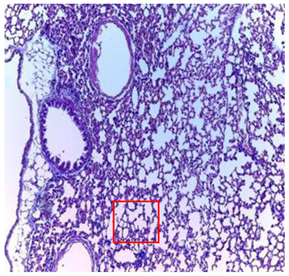

| Lung | ![]() | ![]() | ![]() |

| A pulmonary parenchyma, made of optically empty cavity (alveoli) separated by fibrous septa | Lung parenchyma seat of vascular congestion The vessels have a hyalinised wall with the presence of haemorrhagic diffusion. | Presence of vascular congestion Presence of lymphocytes inflammatory infiltrate | |